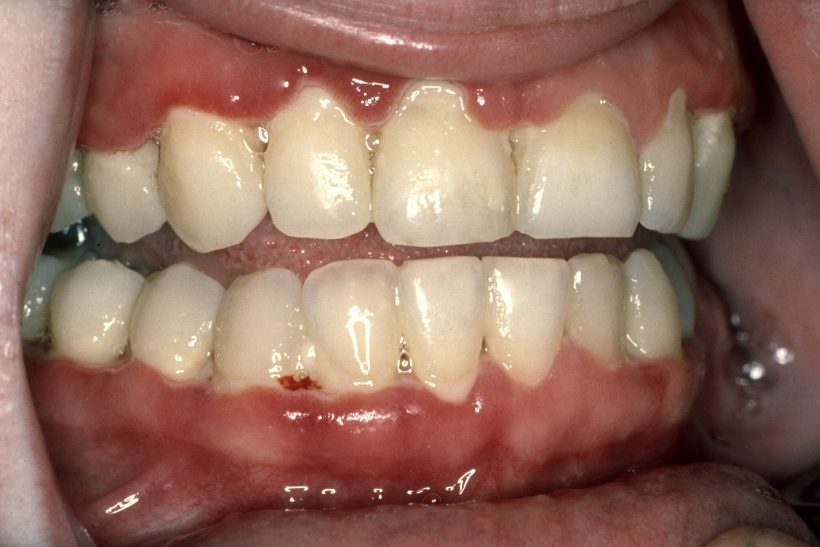

Casi siempre está patología de inicia con el dolor en las encías, y la aparición de halitosis, las encías comienzan a ulcerarse y el tejido se vuelve muerto de color grisáceo, es común que duelan muchísimo las encías que las hace sangrar, y que nos duela al comer y deglutir.